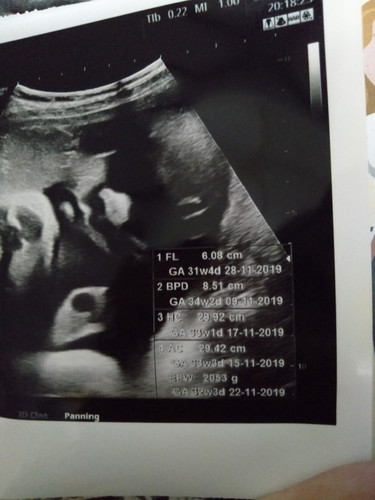

อายุครรภ์จริง

เราลืมถามหมอ อายุครรภ์จริงเราดูตรงไหนค่ะ?

จริงๆ ต้องดูที่ GA แต่ด้วยน้องตัวโตขึ้น เครื่องอัลตราซาวด์จะประมาณอายุครรภ์ตามน้ำหนักตัวน้อง แม่ต้องนับอายุครรภ์ตามประจำเดือนครั้งสุดท้ายค่ะ